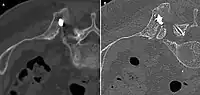

Scanner d'une métastase ostéocondensante dans l'os du crâne d'un patient souffrant d'un carcinome de la prostate. On reconnaît clairement l'extension de la métastase au-delà des limites initiales de l’os.

Scanner d'une métastase ostéocondensante dans l'os du crâne d'un patient souffrant d'un carcinome de la prostate. On reconnaît clairement l'extension de la métastase au-delà des limites initiales de l’os. Par comparaison, scanner de métastases ostéolytiques dans l'os du crâne d'une patiente souffrant d'un cancer du sein. On distingue une ostéolyse plus grande sur le front, et plusieurs plus petites.

Par comparaison, scanner de métastases ostéolytiques dans l'os du crâne d'une patiente souffrant d'un cancer du sein. On distingue une ostéolyse plus grande sur le front, et plusieurs plus petites. Radio du bassin d'un patient atteint d'un carcinome de la prostate : multiples métastases ostéocondensantes, en particulier sur le sacrum, mais aussi sur l'ilion surtout gauche (à dr. sur l'image), sur la pointe de l'ischion gauche, et sur le fémur proximal gauche. On détecte à l'occasion une arthrose de hanche droite (à g. sur l'image).

Radio du bassin d'un patient atteint d'un carcinome de la prostate : multiples métastases ostéocondensantes, en particulier sur le sacrum, mais aussi sur l'ilion surtout gauche (à dr. sur l'image), sur la pointe de l'ischion gauche, et sur le fémur proximal gauche. On détecte à l'occasion une arthrose de hanche droite (à g. sur l'image). Radio du bassin avec métastases ostéolytiques. Les métastases sont sur les deux fémurs et sur le bassin lui-même.